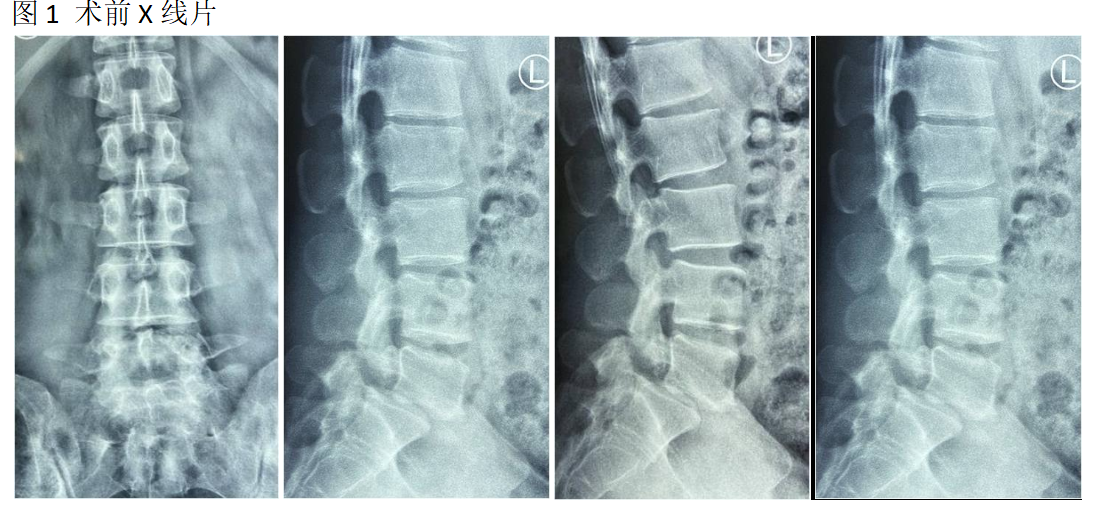

王XX,男,29岁。

主诉:腰疼及左下肢疼痛麻木1年,加重2个月。

查体:L4-5-s1棘间及椎旁压痛,双下肢直腿抬高试验阴性,双下肢肌力肌张力正常。